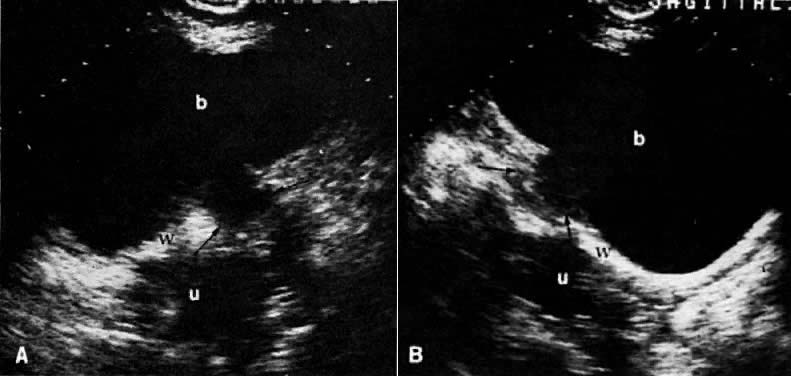

Ultrasound may play a role in the evaluation of tumor extension to the parametrium and the pelvic sidewall in patients with an equivocal pelvic examination.38,39 In stage IB, the tumor is confined to the cervix on ultrasound, without parametrial extension (see Fig. 5B and C). In stage IIB, a tongue of the hypoechoic soft-tissue mass extends laterally from the cervix (see Fig. 6B). More recently, high-resolution transrectal ultrasound was found to be more sensitive in assessing parametrial tumor spread compared to clinical evaluation (78% vs 52%, respectively).40 Ultrasound is also capable of detecting tumor extension into the bladder (Fig. 20),39,41 hydronephrosis (Fig. 6C),38 and/or ureteral obstruction (see Fig. 6B). Unlike CT, however, it cannot always reliably evaluate the level and cause of the obstruction.

Fig. 20. Metastatic breast carcinoma with adnexal metastases and bladder wall invasion. Transverse ( A) and sagittal ( B) sonograms of the pelvis show an irregular hypoechoic adnexal mass ( arrows) invading the bladder wall ( w ). ( b, bladder; u, uterus.)